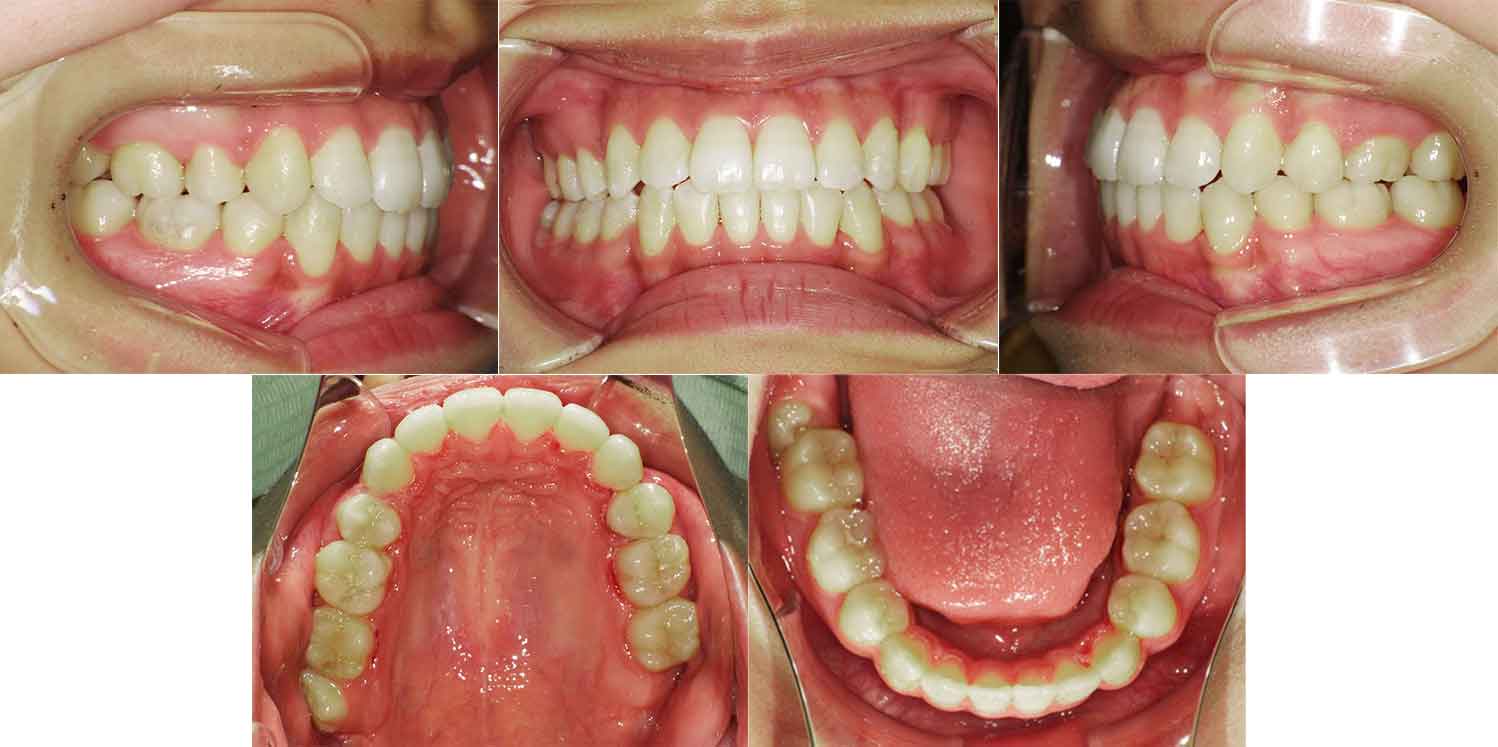

横浜市にお住まいの20代の女性の症例をご紹介。前歯のガタガタと開咬で悩まれている患者さんでした。上下左右の4番目の歯(第一小臼歯)を抜歯して舌側矯正(裏側矯正)でアンカースクリューと顎間ゴム(エラスティック)を併用して改善しました。

治療前

| 主訴 |

前歯にガタガタがあって、かみ切れない |

| 診断名 |

叢生(ガタガタ、でこぼこ) |

| 治療の方法 |

舌側矯正(裏側矯正)+アンカースクリュー |

| 患者様の年齢 |

20代女性 |

| 治療期間 |

2年4か月 |

| 治療の説明 |

ガタガタ、前歯でかめないことを主訴に当院を受診されました。 |